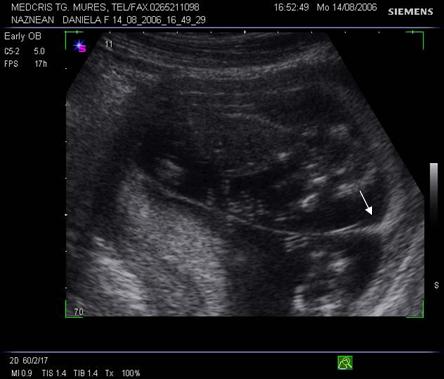

Fig nr 36 Sarcina gemelara biamniotica, 6 sapt, cu 2

saci amniotici si 2 embrioni (cu sageata )